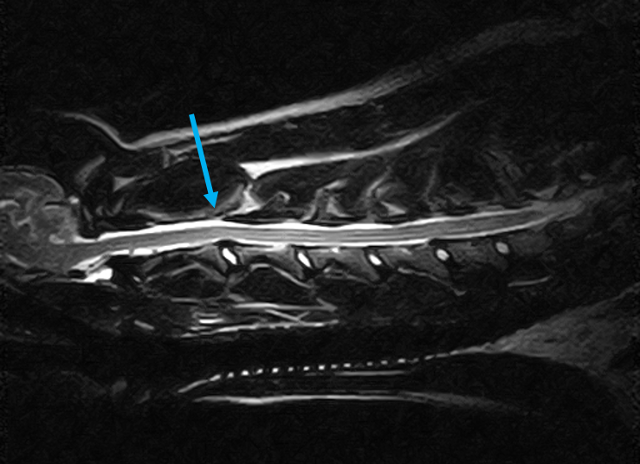

W obrębie kanału kręgowego najczęstszymi wskazaniami do badania rezonansem magnetycznym u zwierząt są:

• ocena rdzenia kręgowego, splotów i nerwów rdzeniowych

• ocena przepukliny i stopnia ucisku na rdzeń kręgowy

• dyskopatie, neuropatie, radikulopatie

• urazy kręgosłupa